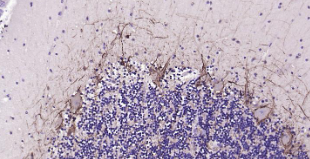

Immunohistochemical analysis of paraffin embedded human cerebellum tissue slide using IHC0218H (Human NF-M IHC Kit).